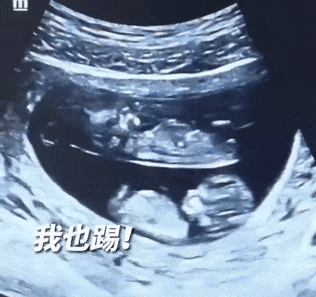

有網友曬出了他們的B超照

十分有趣

視頻中

兩個寶寶在母親的肚子里

呈上下分布

并且還不停踢動

對此網友評論調侃

“原來雙胞胎還有‘上下鋪’啊!”

“從網友發布的視頻來看,兩個胎兒在媽媽肚子里各占一間房,這是很常見的,是典型的‘雙羊’。”朱霞說,但像這么規整地看似“上下鋪”的,確實很少見,80%至90%是左右“分房”,雙胞胎在孕媽子宮內也會呈現不同的姿勢。